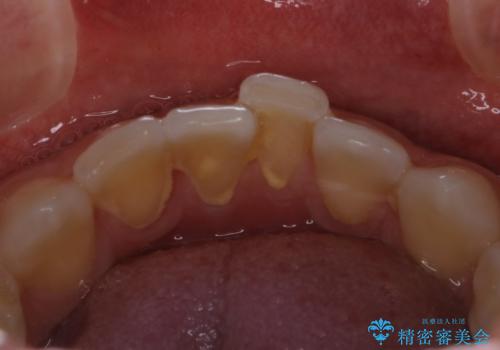

- 歯医者でのクリーニングはかなり久しぶりで、今後虫歯の治療もしていくので綺麗にしたいとのことでした。PMTC30分コースを行いました。

日々の磨き残しや唾液の成分などによりバイオフィルムや歯石はどうしても付着してしまいます。歯石や汚れを放置していると、そこで病原菌が繁殖す始めます。歯肉に炎症が生じると歯周病などの引き金となります。

そのため、2~3か月に1回は、歯科医院での専門的クリーニングをすることが大切です。